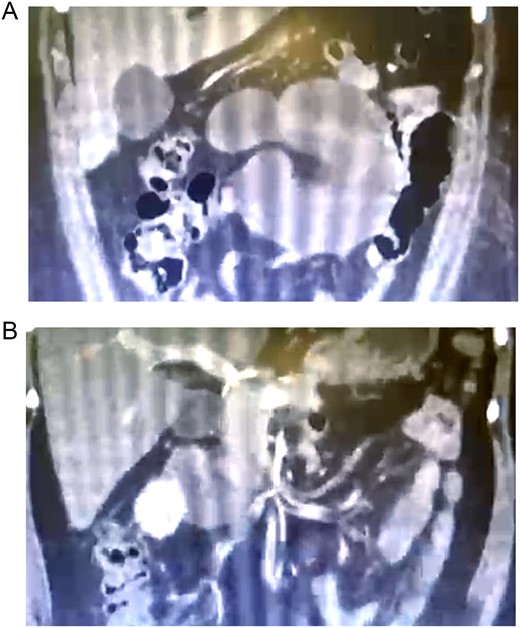

A 36 year-old woman with a history of obesity, gastroesophageal reflux, and hiatal hernia who underwent laparoscopic Roux-en-Y gastric bypass with hiatoplasty was discharged at 24 hours after surgery without complications. Three days later, the patient presented to the emergency room with complaint of sudden high-intensity postprandial abdominal pain of a colicky type, localized in the epigastrium and radiating to the hypogastrium, accompanied by abdominal distension and lack of flatus. Physical examination revealed a dry oral mucosa, pale skin, decreased vesicular breath sounds in both lungs, tense abdomen in the superior hemiabdomen, and diffuse tenderness on palpation with absent hydro-aerial sounds. Contrast CT of the abdomen and pelvis revealed dilated intestinal loops that were congested and associated with torsion and congestion of the mesenteric vessels, herniation of intestinal loops toward the space posterior to the gastrojejunostomy, and a moderate amount of free fluid in the pelvic cavity. There was no evidence of free air (Fig. 1A and B). The patient was referred for surgical revision.

(A) Abdominal tomography showing herniation of the intestinal loops toward the space posterior to the gastrojejunostomy; (B) dilated and congested intestinal loops associated with torsion and congestion of mesenteric vessels.